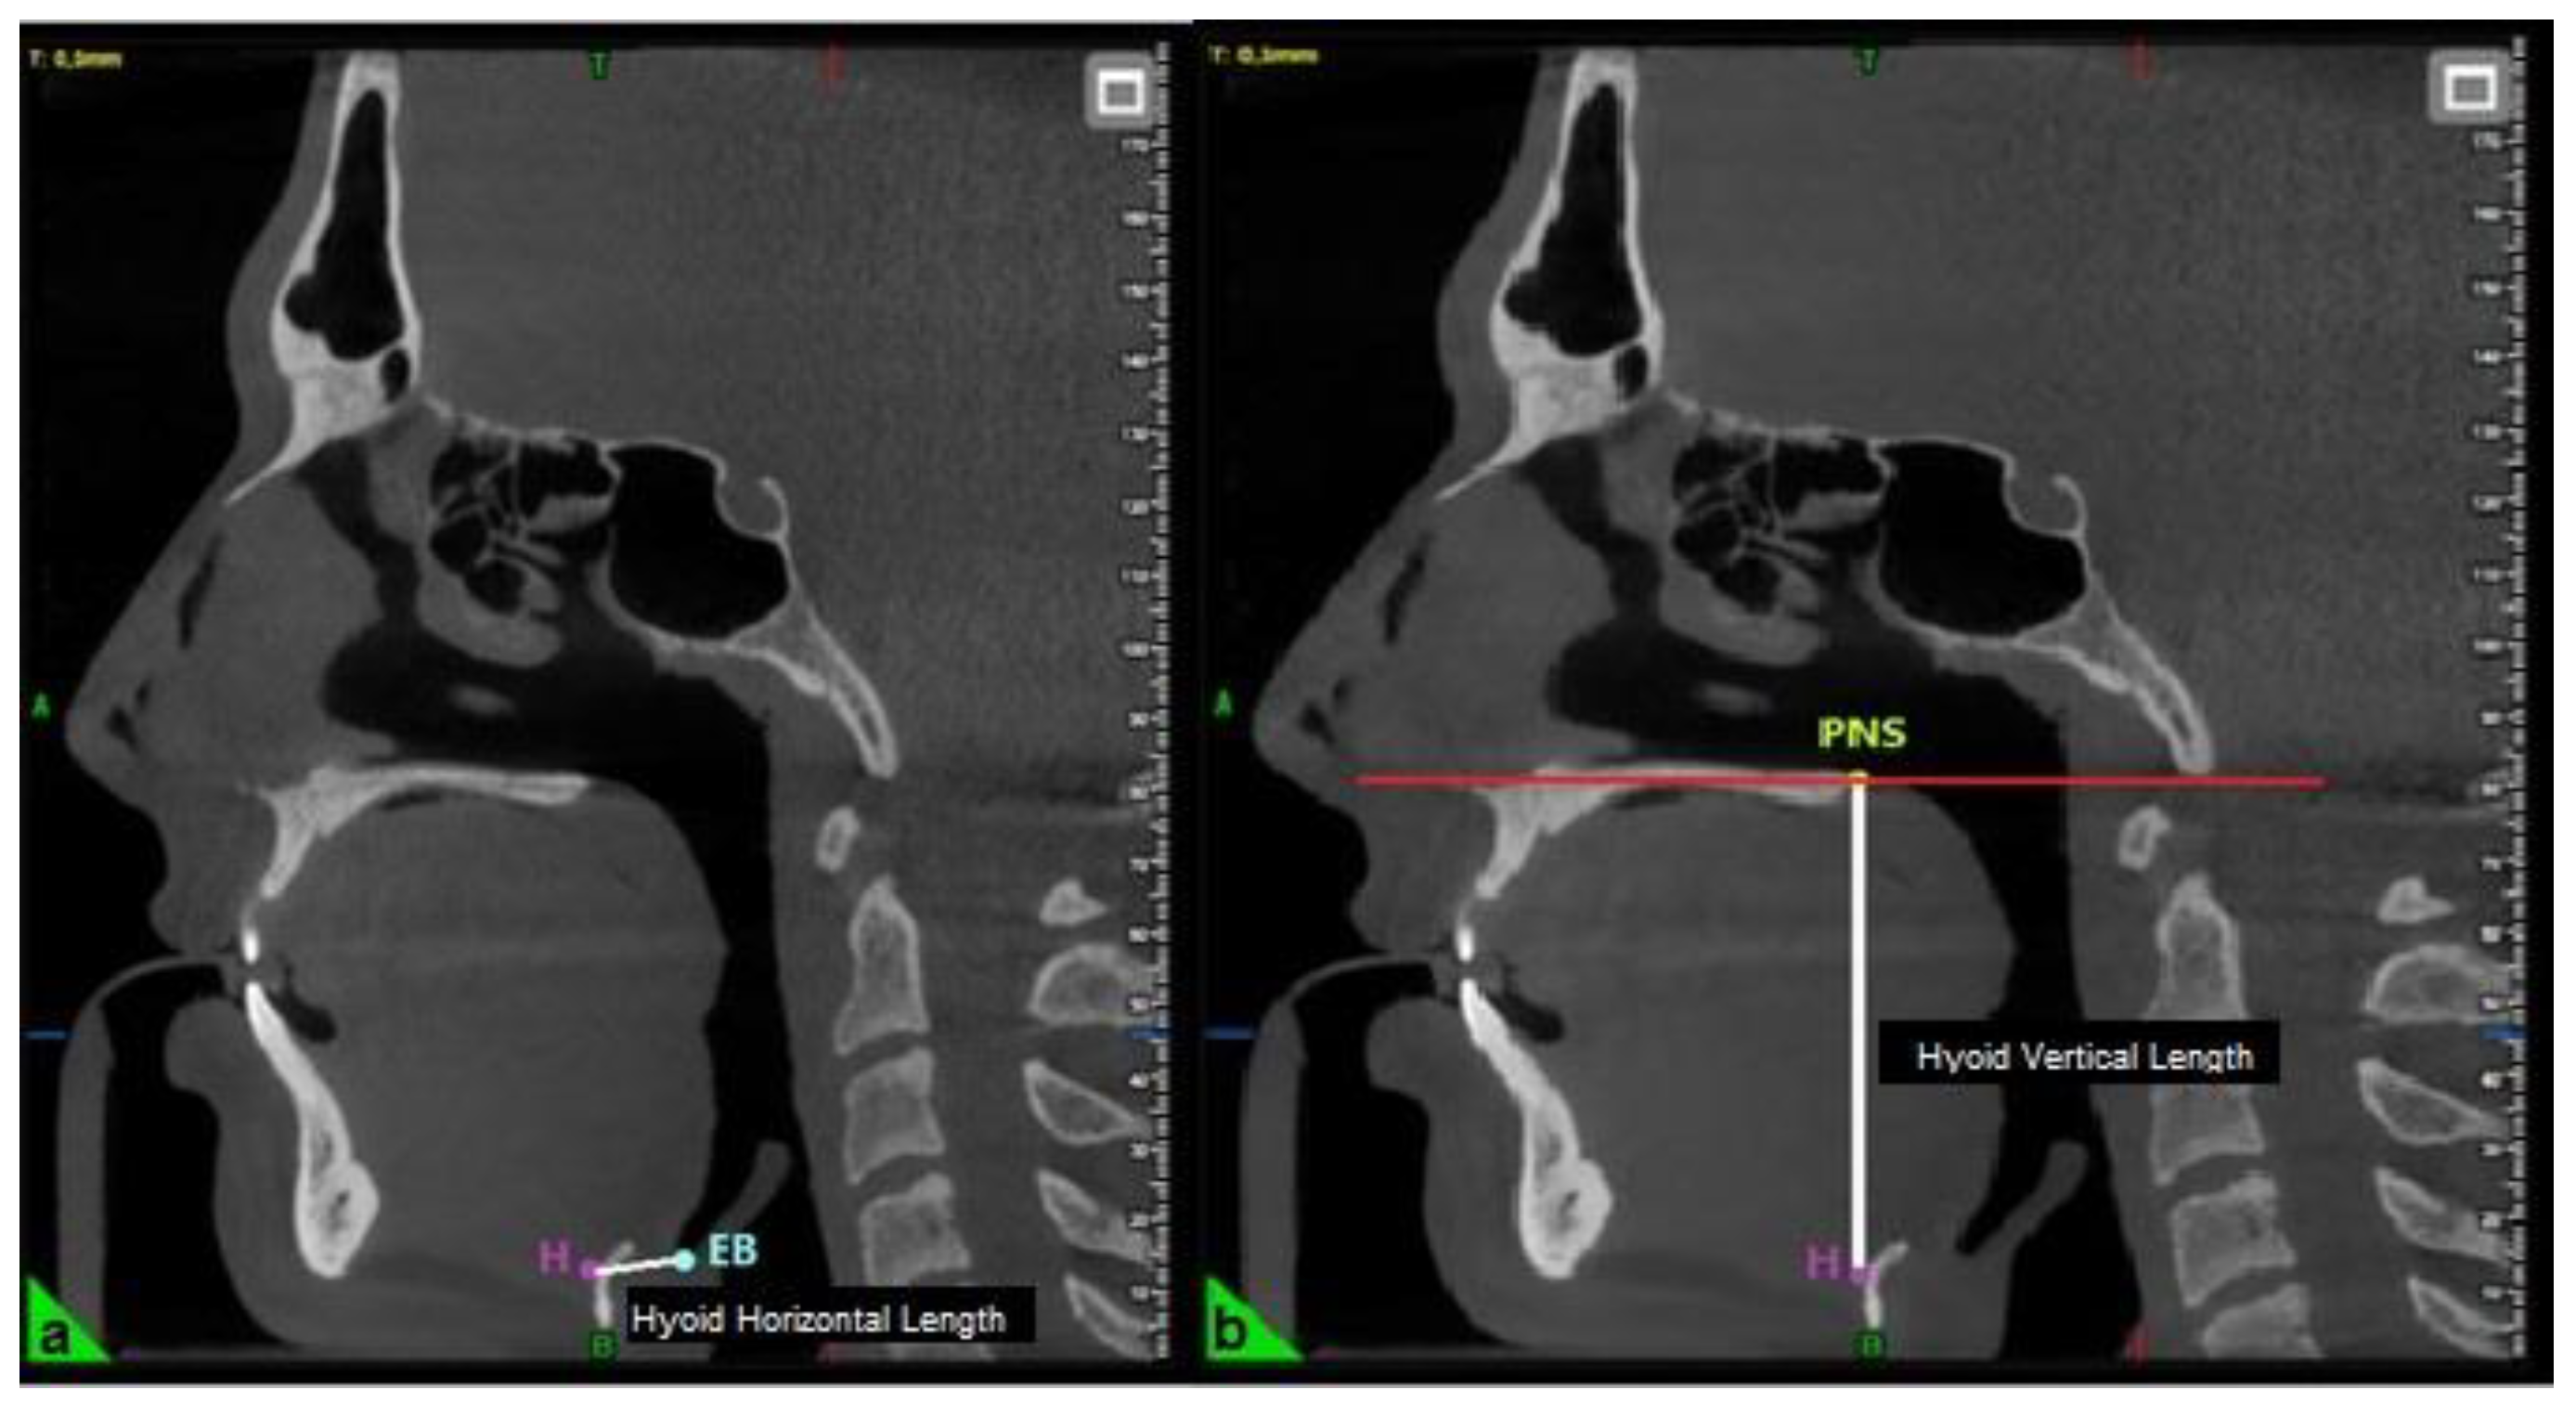

Three-Dimensional Cephalometric Measurements

| Hyoid Horizontal Length (mm) | 14.08 ± 3.08 |

| Hyoid Vertical Length (mm) | 62.87 ± 8.14 |